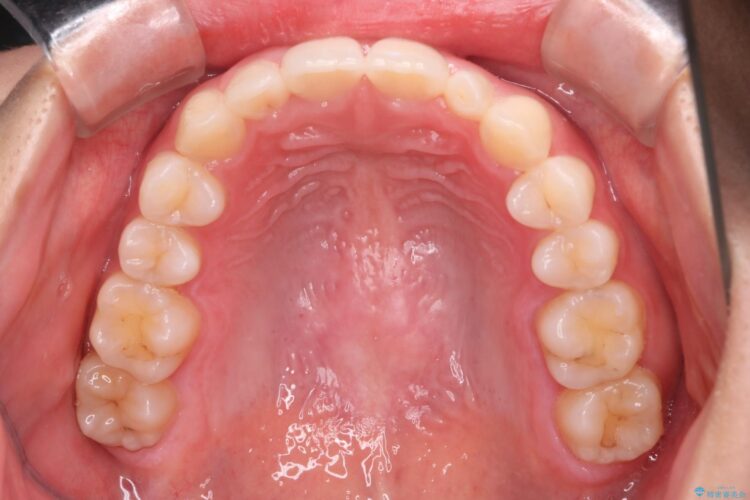

前歯のガタつきを改善するのに時間がかかりましたが、ガタつきもかみ合わせも綺麗になりました。

患者様の希望で、矯正終了後にホワイトニングも行い歯の色味も自然な白さになりました。